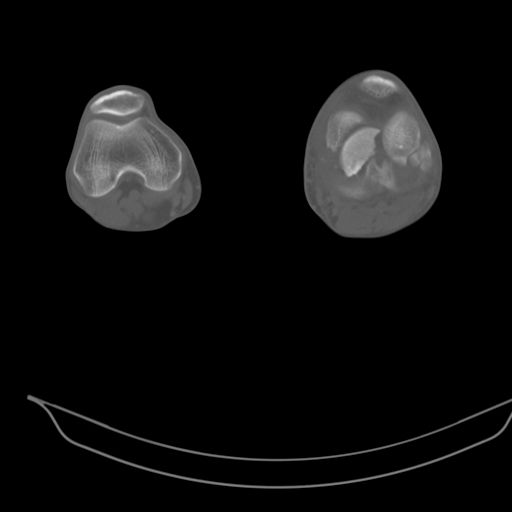

CT shows major bony fragments which are markedly rotated .With this amount of bony damage,you probably should attempt to get reasonably loooking knee with ORIF and thn if he needs a TKR due to pain a few years from now, then tleast you have something looking like a knee that you can replace rather than having to use revision knee for a primary TKR now. 4 weeks is not too long .what is the condition of soft tissues?

При внутрисуcтавных переломах трехмерные (3D) изображения, кроме красивого снимка, не дают полную информацию о состоянии отломков, самыми информативными являются корональные срезы на КТ и обычная длинная ренгенограмма конечности для сравнения оси конечности.

Фронтальные внутрисуставные переломы мыщельков бедра, так называемые Hoffa fracture, не частые, но встречающиеся переломы, в основном они связаны с травмой высокой энергией.

В зависимости от смещения рекомендуется сопоставление костных фрагментов с последующей жесткой фиксацией.

В вашем случае доступ будет медиальный, сопоставить развернутый медиальный мыщелок и фиксацию надо произвести в передне-заднем

направлении шурупами 4.5 мм в диаметре, углубив головку шурупов под хрящ, а поперечную фиксацию - межмыщелковыми шурупами. Желательно применить шурупы 6.3 мм в диаметре. Дополнительная Buttress technique пластина предотвратит перелом от скольжения.

Даже при сросшемся переломе мыщелка рекомендуется реконструктивная операция для предотвращения последующих варус или вальгус деформации.

Место образовавшего костного дефекта после разворота мышелка заполняется спонгиозной аутокостью. Костная пластика применяется даже

в свежем случае.